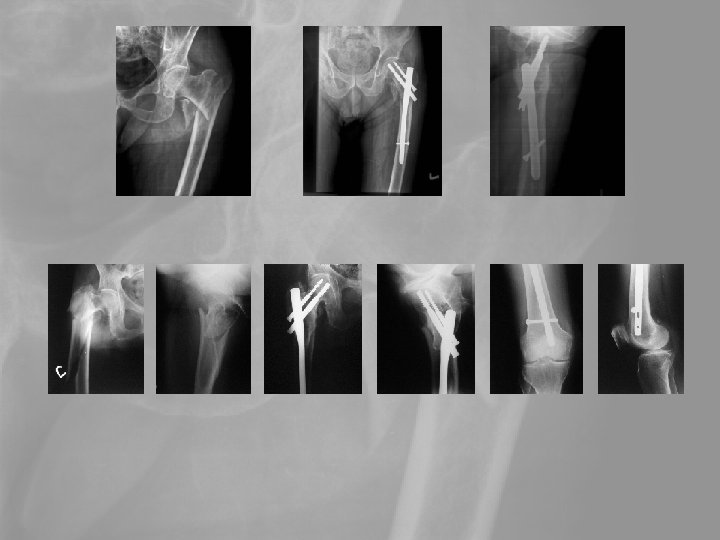

5. Medence, csípótáji törések A csípőtáji törések a leggyakrabban előforduló időskori törések. A tokon belüli törés szövődménye a fejelhalás, ami az esetek 25 -35 %-ában bekövetkezik. A tokon kívüli törések gyógyhajlama jó. A leggyakoribb szövődmény a thromboembolia, mely a az első postoperatív évben 20 -25%-os halálozással jár.

Delayed revision 73 y female. Failed primary stabilisation, Delayed septic complication Pyarthros coxae, septic diaphyseal nonunion. Exarticulation?

Delayed revision Op. sec. Girdlestone+open plate-osy. Secondary wound granulation

Keresztek… T. M. 60 é. Nő -6 év: Fr. cruris l. s. Műtétek: Felfúráros velőűrszegezés UTN ENDER-szegezés, fibula-OT ASP DC-lemezelés ASP Mankóval jár 2006 05 10 fémkivétel, decorticatio, ASP Sebgyógyulás után járógipsz 2006 07 07 Kontroll: gipszeltáv. 2006 07 17 fedett FRVSZ 2006. 09. 08 Kontroll: 1 bottal jár a biztonságért. Térdflexio 0 -120, bokamozgás 0 -0 -30. Terhelve járhat, kontroll decemberben, pénteki napon

67é nő, szártörés, -2év, 3 revisio, fertőzés 85é nő, önellátó, 2 bottal jár Keresztek…